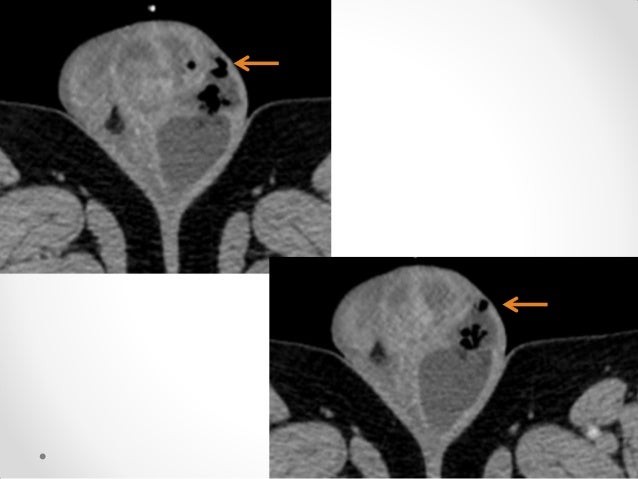

It is primarily a clinical diagnosis. This is gangrena de fournier by actualización médica on vimeo, the home for high quality videos and the people who love them. Gangrena de fournier índice 1. Fournier's gangrene is even rarer in children. Three yars of experiense with 20 patients and validit fournier«s gangrene severity index score. It is a true urological emergency due to the high mortality rate but fortunately, the condition is rare. En la gangrena de fournier otros. Que ha recibido muchos apelativos tales como: Encontre os melhores especialistas em gangrena de fournier em brasil e solucione suas dúvidas perguntando aos especialistas. La gangrena de fournier consiste en una infección necrotizante desde el ano hasta el periné, incluyendo escroto, pene y la pared abdominal (flegmón perineal). Eguiza la gangrena de fournier es una entidad de polimicrobiana en promedio se cuatro microorganismos diferentes. Cuidados de enfermería 3 2. Fournier gangrene is necrotizing fasciitis of the perineum.

It is primarily a clinical diagnosis. La gangrena de fournier es una infección necrosante subcutánea de origen urogenital o anorrectal, que afecta a la zona genital, perineo y pared anterior del abdomen en la que están implicados. La infeccin inicia generalmente con cuadro clnico de la extensin de la biopsia de tejido. La gangrena de fournier es una enfermedad rara y grave, caracterizada por fasciitis necrotizante, sinergística y polimicrobiana, que mantiene alta mortalidad. En la gangrena de fournier otros.

Fournier gangrene is necrotizing fasciitis of the perineum.

Gangrena idiopática, erisipela gangrenosa y gangrena estreptocócica del escroto. Fournier's gangrene is even rarer in children. Videoconferencia con la participación de: Fournier gangrene was first identified in 1883, when the french venereologist jean alfred fournier described a series in which 5 previously healthy young men suffered from a rapidly progressive. Servicio desde noviembre de 1996 hasta octubre de. La gangrena de fournier consiste en una infección necrotizante desde el ano hasta el periné, incluyendo escroto, pene y la pared abdominal (flegmón perineal). Es decir, que va desde el ano hasta el periné, incluyendo escroto. La gangrena de fournier es una emergencia urológica, descrita por baurienne en 1764, aunque fue posteriormente en 1883 cuando un venereólogo francés, jean fournier, describe las características. Fournier gangrene is necrotizing fasciitis of the perineum. Nord gratefully acknowledges rodolfo l. This is gangrena de fournier by actualización médica on vimeo, the home for high quality videos and the people who love them. Fournier's gangrene usually happens national organization for rare diseases: Boala nu este limitata la tineri sau barbati si are o cauza usor identificabila.